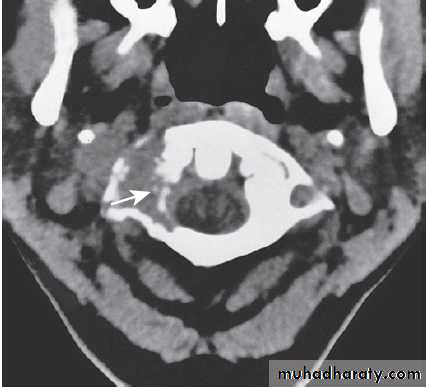

Fig. Different techniques of imaging the head and brain. A Skull X-ray showing lytic skull lesion (eosinophilic granuloma – arrow). B CT

showing complete middle cerebral artery infarct (arrows). C MRI showing widespread areas of high signal in multiple sclerosis (arrows). D SPECT after

caudate infarct showing relative hypoperfusion of overlying right cerebral cortex (arrows).